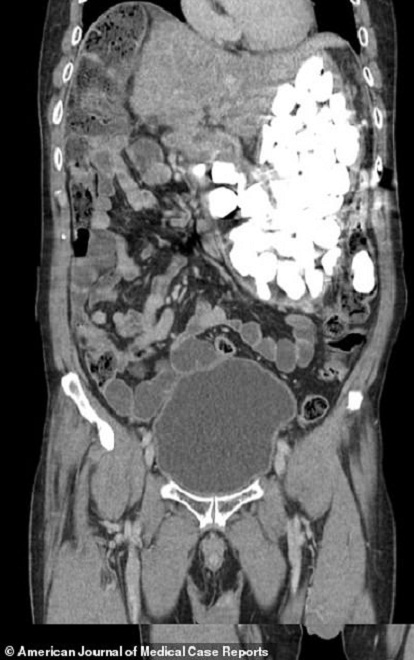

Ảnh chụp cho thấy dạ dày của người đàn ông bị lấp đầy bằng sỏi đá, đồng xu và nắp chai

Kết quả chụp ổ bụng sau đó cho thấy những dị vật đã chiếm lấy toàn bộ dạ dày của bệnh nhân.

Khối lượng sỏi đá và đồng xu người đàn ông nuốt vào bụng lên tới 2kg